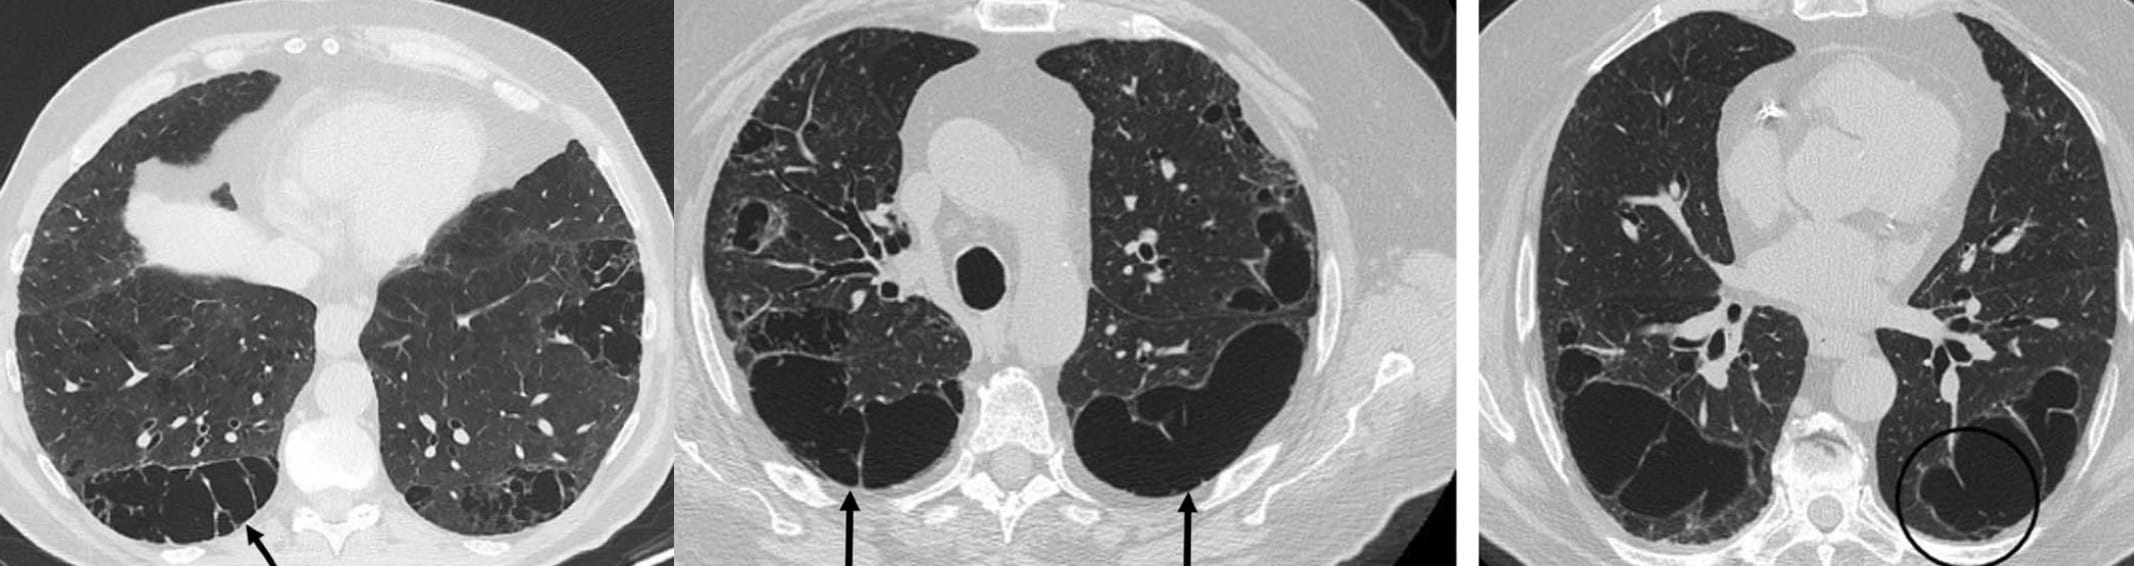

The evolution of pulmonary histiocytosis (PLCH) accounts for the imaging findings:

Key Points

Note the predominant involvement of the upper lungs.

The very definition of an Aunt Minnie

Another Aunt Minnie

One observation seems relevant: the cystic spaces may be situated away from the pleural surface.